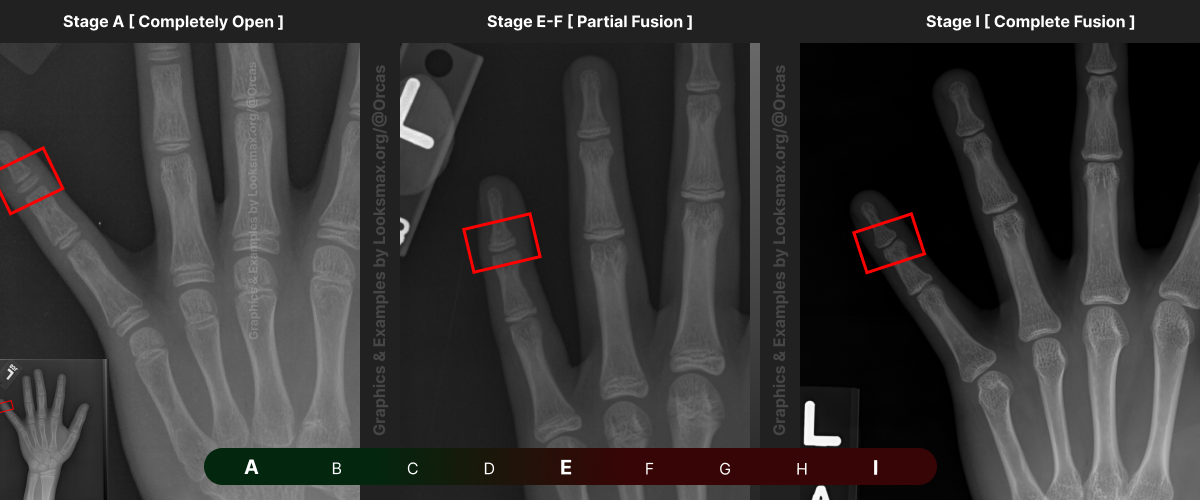

I added references for stages A (Completely unfused), E-F (Partial fusion, basically late stages of puberty), and I (Complete Fusion)

You will have to eyeball this now using your own xrays, I’ve given three examples and some wiggle-room for letters using a reference bar (green-red) below the image, write down your estimated guesses in a text file until you finish all 13 bones.

Don’t doubt yourself, eyeballing isn’t perfect but it still works well, just choose & continue.

Ex.

“My Radius looks more fused than the image from E-F, but its not as fused as I, it’s closer to the 2nd picture though, so I’ll rate it G” And continue

Bonetype: Radius (distal end)

Bonetype: 1st Metacarpal (thumb)